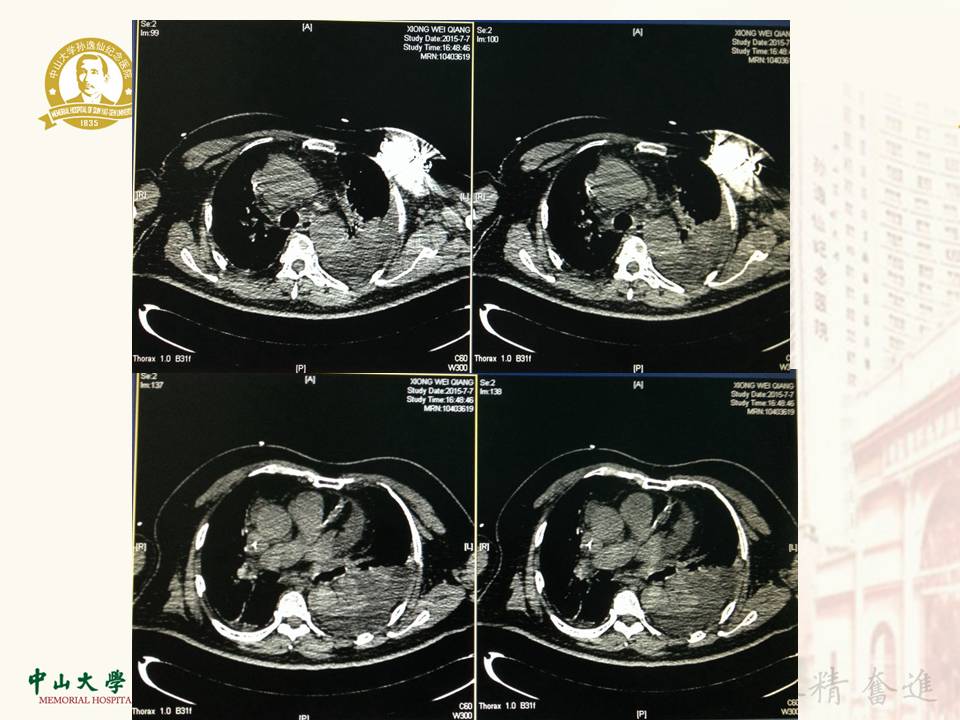

心外膜室速消融一例